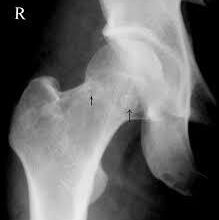

هناك أنواع عديدة من أمراض العظام. الأكثر شيوعًا هو هشاشة العظام (AH-stee-oh-por-OH-sis). مع هشاشة العظام ، تصبح عظامنا ضعيفة وأكثر عرضة للكسر. غالبًا ما يكسر الأشخاص المصابون بهشاشة العظام عظام الرسغ والعمود الفقري والورك.

كثير من الناس لديهم عظام ضعيفة ولا يعرفون ذلك. ذلك لأن فقدان العظام يحدث غالبًا على مدى فترة طويلة من الزمن ولا يؤلم. بالنسبة للعديد من الأشخاص ، فإن كسر العظام هو أول علامة على إصابتهم بهشاشة العظام.

نظرًا لأن هشاشة العظام لا تظهر عليها أي أعراض حتى تنكسر العظام ، فمن المهم التحدث إلى طبيبك حول صحة عظامك. إذا شعر طبيبك أنك معرض لخطر الإصابة بهشاشة العظام ، فقد يطلب إجراء اختبار كثافة العظام. يقيس اختبار كثافة العظام مدى قوة – أو كثافة – عظامك وما إذا كنت مصابًا بهشاشة العظام. يمكن أن يخبرك أيضًا عن فرص إصابتك بكسر في العظام. اختبارات كثافة العظام سريعة وآمنة وغير مؤلمة.